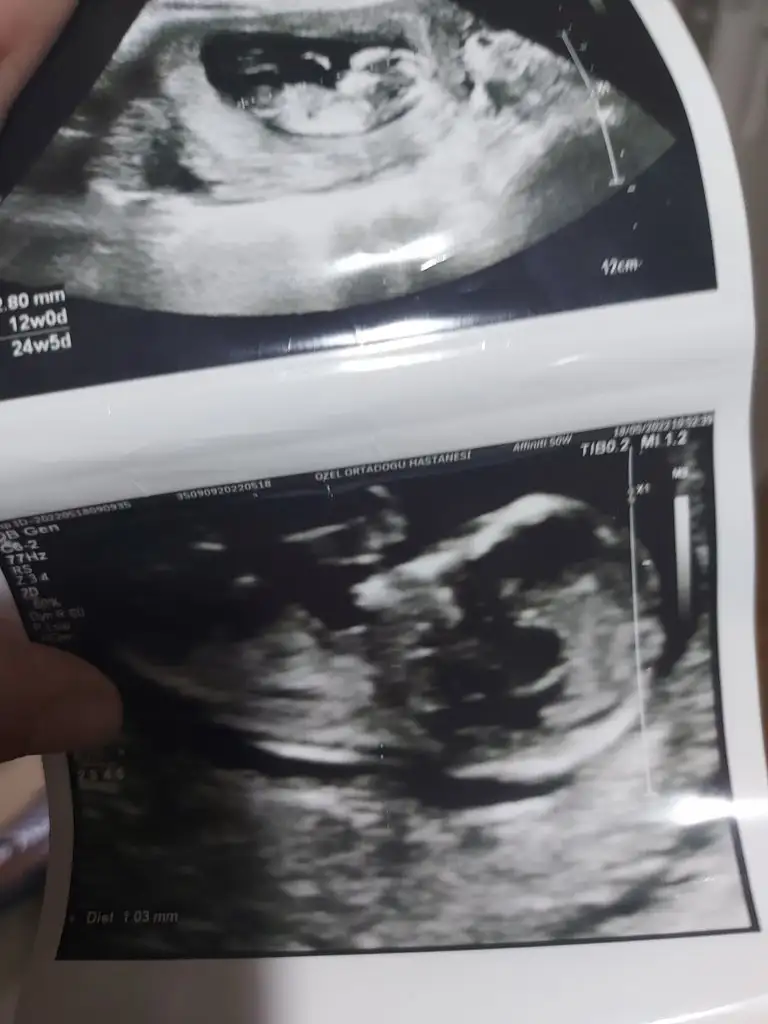

5 ve 14. haftaya kadar olan ultrason fotolarınızı paylaşın. Vajinadan mı yoksa karından mı çekildiğini ve kaç haftalık olduğunu da mutlaka belirtin.

Karından çekildi 6+3 :)Selam Kızlarbir çok kişi gruplardan beni bilir. Yine yetiştim imdatlara

yolk sac nasıl değiştirmiş yeriniKarından çekildi 6+3 :)

9 haftalık karında